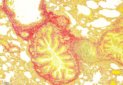

Safranon-O_Mouse-Knee__viewcapture-3